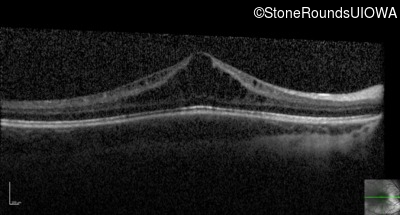

Optical Coherence Tomography - Right - 20/50

Exemplar / OCT Stack